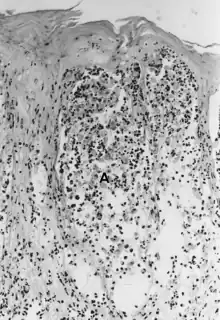

Foot-and-mouth disease - acantholysis in a sample of a skin vesicle: Necrosis of the stratum spinosum can be observed, and keratinocytes floating in the vesicular fluid (spongiosa).

Acantholysis is the loss of intercellular connections, such as desmosomes, resulting in loss of cohesion between keratinocytes,[1] seen in diseases such as pemphigus vulgaris.[2] It is absent in bullous pemphigoid, making it useful for differential diagnosis.

This histological feature is also seen in herpes simplex infections (HSV 1 and 2) and varicella zoster infections (chicken pox and shingles).